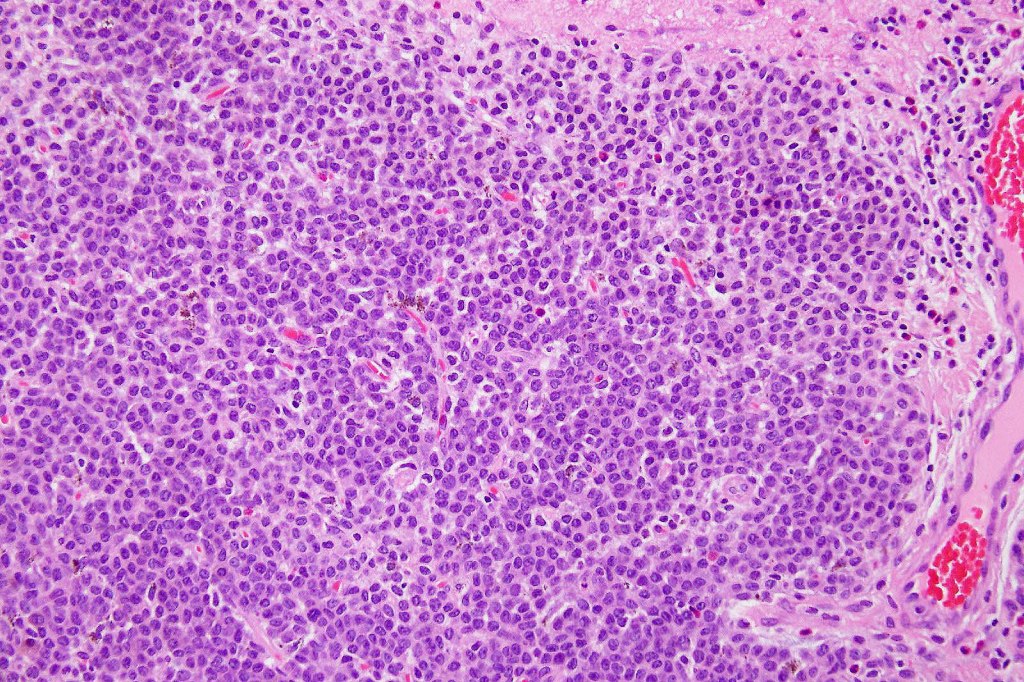

This melanoma arose in a small congenital nevus of the scalp. It metastasized widely. Varying features in different fields.